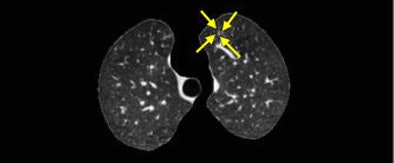

| Nodules detected by ROI detection system. Top, small nodule with inconspicuous intensity difference with surrounding lung context. Below, small well-formed nodule. Third from top, small nodule hardly distinguishable from the background and nearby thin vessels. Bottom, small irregularly shaped nodule. All images courtesy of Javad Alirezaie, Ph.D. |